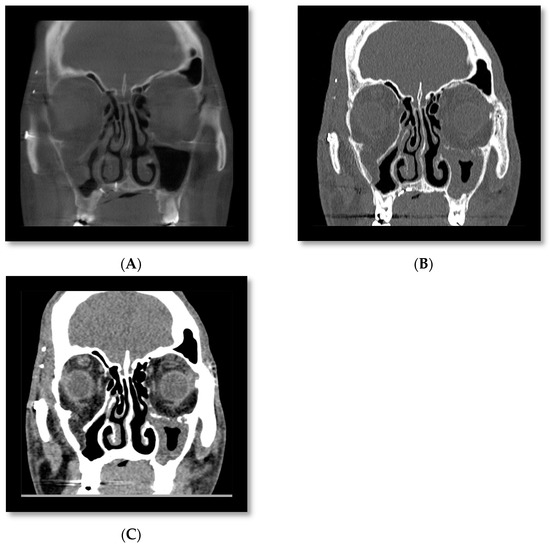

3.5. Cone Beam CT for Assessment of Nasal Fractures

3.6. Cone Beam CT for Assessment Fractures of the Zygomatic Maxillary Complex and Midface